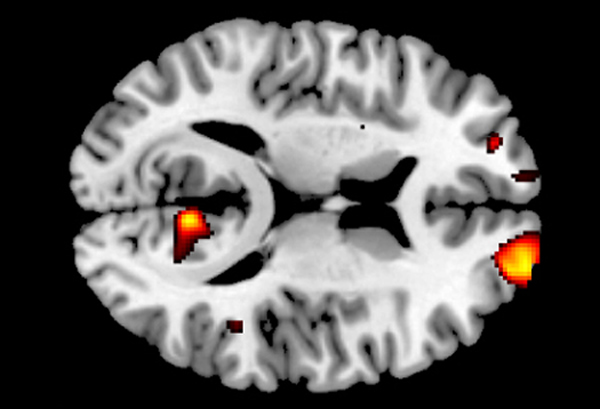

瑞士苏黎世大学的研究人员近日发现,大脑内顶叶和颞叶结合处有更多灰质的人更无私。这项研究首次表明了大脑解剖、大脑活动和利他行为之间存在着联系。

这项研究的目的是要找出为什么有这种差异。以往的研究表明,大脑的某些区域—顶叶和颞叶交汇的地方与一个人换位思考的能力有关。利他主义者在了解他人的想法和感受的能力更强。因此,研究人员认为,大脑中这部分的个体差异可能与利他行为的差异有关。苏黎世大学经济学系博士后研究员Yosuke Morishima说:“表现更无私的人在大脑的顶叶和颞叶结合处有更多的灰质。”

这项研究的志愿者在决定如何分钱时,他们的大脑活动有着明显的差异。自私的人在做出一些利他行为时,耳后的大脑区域就变得非常活跃了;而利他主义者在付出的代价非常高时,该大脑区域才变得比之前活跃。因此,当人们达到他们的无私行为意愿的极限时,这部分的大脑区域才被激活得特别强烈。